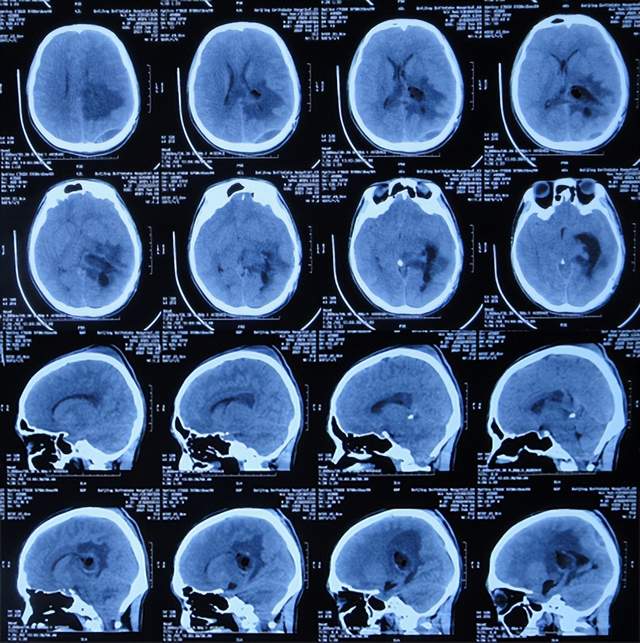

第2次出院后5个月即2022年6月初,再次出现头痛的症状,因左侧颞角再次增大,于2022年7月18日,第3次来到李小勇脑脊液科治疗。入院时:仅时有头痛。查头颅CT示左侧颞角扩张(图-33)。

图-33:2022年7月18日头颅CT

入院后3天即2022年7月21日,显微镜下颞角脉络丛切除术+分流管调整术,留置引流一根;术后查头颅CT示脑室内有2根管(图-34)。

图-34:2022年7月21日头颅CT

入院后11天即2022年7月29日(脉络丛切除术后8天),查头颅CT示引流术后状态(图-35)。

图-35:2022年7月29日头颅CT

入院治疗12天即2022年7月30日(脉络丛切除术后9天),给予拔除了原脑室腹腔分流管,查头颅CT示脑室内有一根管(图-36)。

图-36:2022年7月30日头颅CT

入院治疗21天即2022年8月8日(脉络丛切除术后18天),查头颅CT未见异常(图-37),患者身体无异常(图-38)。

图-37:2022年8月8日头颅CT

图-38:2022年8月8日

2022年8月22日(脉络丛切除术后32天),查头颅CT示颞角未见扩张(图-39),给予夹闭引流管。

图-39:2022年8月22日头颅CT

夹闭引流管14天后即2022年9月5日(脉络丛切除术后46天),查头颅CT示未见异常(图-40)。

图-40:2022年9月5日头颅CT

夹闭引流管15天后即2022年9月6日(脉络丛切除术后47天),给予拔除了脑室外引流管,当天查头颅CT示脑室基本正常(图-41);患者身体无异常。

图-41:2022年9月6日头颅CT

拔除了脑室外引流管后6天即2022年9月12日, 查头颅CT示未见异常(图-42);身体一切正常,于2022年9月16日出院。

图-42:2022年9月12日头颅CT

五、出院后随访

出院后3个月即2022年11月,在当地医院查头颅CT示无异常(图-43);本人叙述身体一切正常。

图-43:2022年11月头颅CT